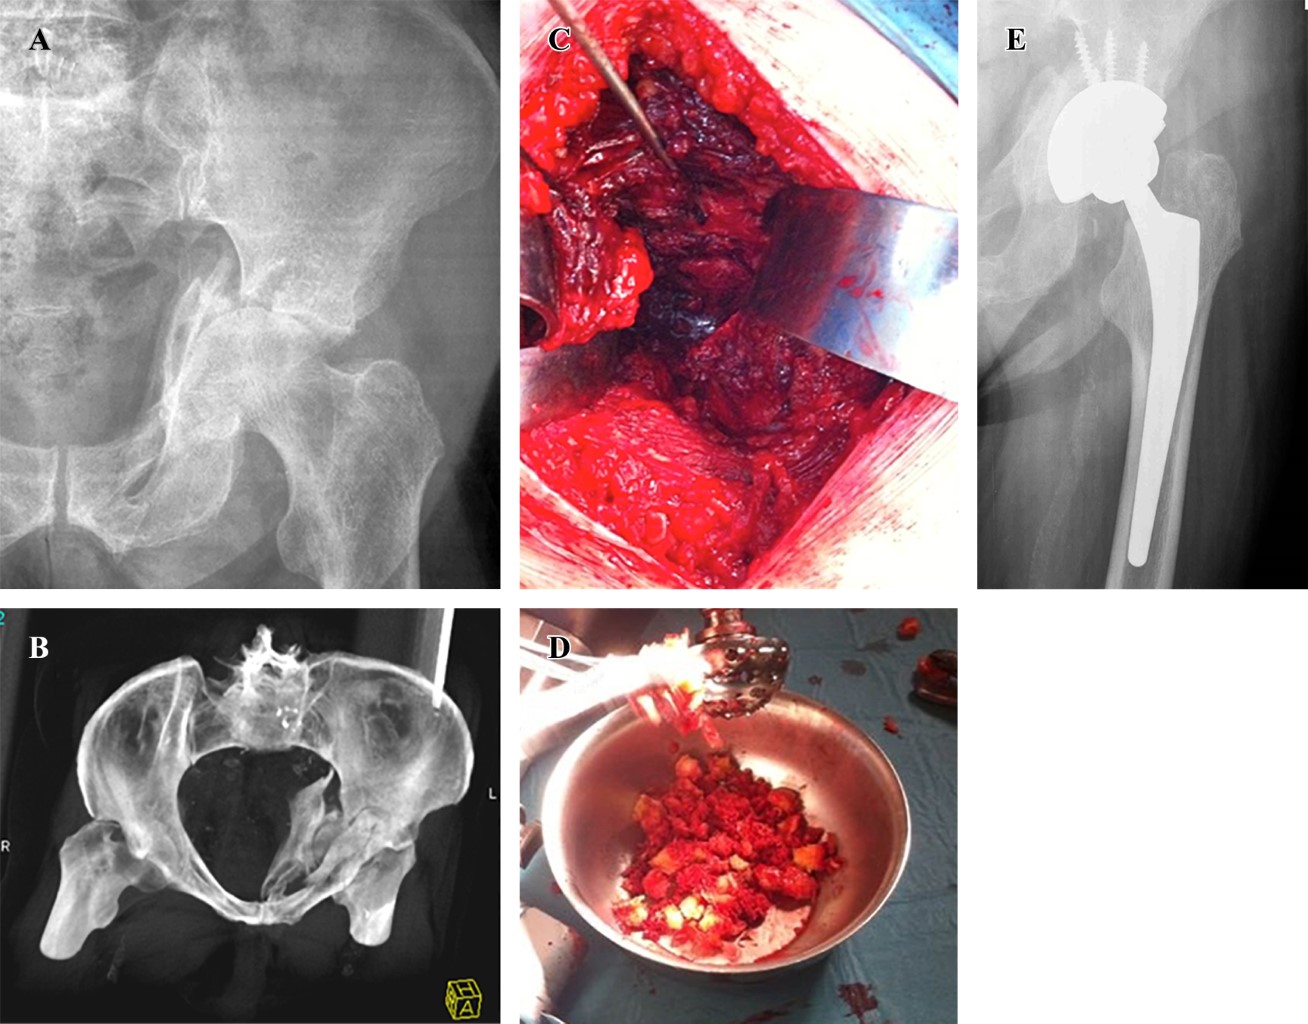

En cuanto al tipo de implante utilizado, en cinco casos se realizó reconstrucción con el concepto "CAGECUP" con una copa de tantalio multihole que permite fijar en múltiples direcciones, media de 56 mm (52-62), fijación con cuatro tornillos (3-5) con cabeza de 36 mm (Figura 1). Las otras dos fracturas requirieron de un implante de reconstrucción tipo anillo de Burch-Schneider (inserto 44 mm, cabeza 28 mm) por elección del cirujano principal debido a que eran fracturas con mayor inestabilidad, un caso de ambas columnas y en una de columna anterior y hemitransversa posterior por el desplazamiento ocurrido entre fragmentos (Figura 2). En todos los casos se utilizó autoinjerto de cabeza de fémur, en uno de los cuales se asoció además a sustituto óseo DBX® (Depuy Synthes) más chips de esponjosa por considerarse autoinjerto cuantitativamente insuficiente. Se implantó vástago cementado en cuatro casos y no cementado en tres (Tabla 2).

Figura 2